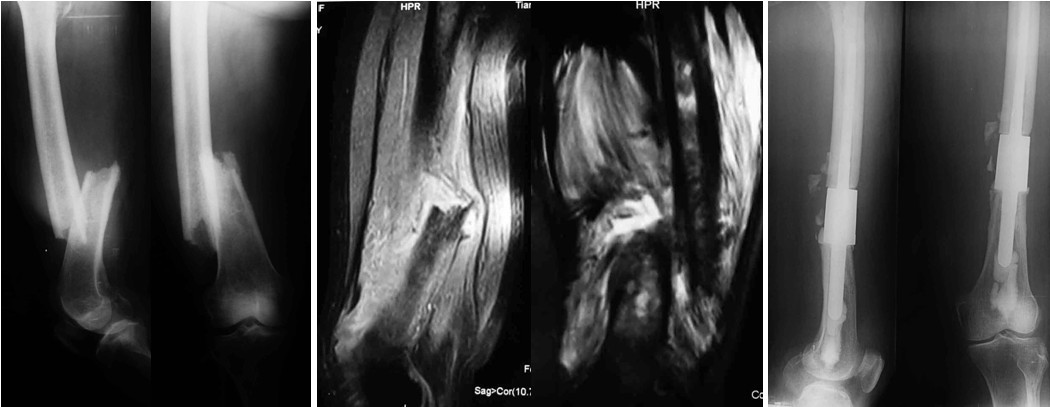

图2女,80岁,右股骨干转移瘤致病理性骨折,肿瘤段切除节段型人工假体重建

节段型人工假体常用于股骨、肱骨,也可用于胫骨或桡骨。手术方法:患者一般取平卧位,股骨、肱骨采用前外侧入路,胫骨和桡骨采用前侧切口。充分显露病变部位,按照术前MRI显示的肿瘤累及范围进行标记,保护周围组织,用电锯切除瘤段骨,取残端组织术中冰冻,确认肿瘤完全切除后,充分扩髓,冲洗,试装假体,假体柄髓内固定部分至少5cm。然后将骨水泥填充髓内腔隙,把涂有骨水泥的假体柄插入髓腔,调整合适位置。待骨水泥凝固后再次冲洗,放入引流管,逐层缝合筋膜、皮下、皮肤即可。股骨恶性肿瘤或转移性肿瘤是节段型人工假体置换的最佳适应证,并发症最少,术后功能恢复最好,文献报道中除了因外伤引起的感染或假体松动外,其他并发症均少见。有些作者并不推荐肱骨和胫骨应用节段型人工假体,原因是肱骨术后旋转应力增加,容易出现假体的无菌性松动;而胫骨位置表浅,软组织覆盖不足,感染、假体脱离、假体骨折、假体周围骨折率等并发症等较高。但是,随着第二代新型肱骨节段型人工假体的设计、腓肠肌皮瓣转移的临床应用,这种限制逐渐被打破,尤其是对于肱骨和胫骨转移性骨肿瘤伴病理性骨折,仅采用姑息性治疗的患者仍是一个比较理想的适应证。桡骨应用非常少见,2010年Simon等第一次报道了桡骨节段型人工假体的临床应用,术后患者腕关节活动范围80°,肘关节活动0~115°;握力恢复正常侧的50%,旋前旋后功能恢复正常。术后两年无假体松动、感染、骨折等并发症。功能按照Mayo评分标准:肘关节80分,腕关节60分,均高于其他桡骨重建方法。